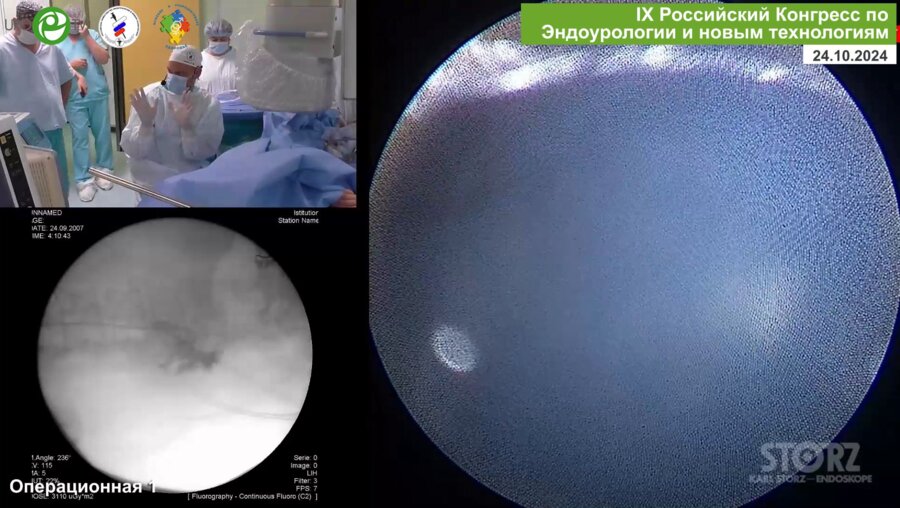

IX Российский Конгресс по Эндоурологии и новым технологиям

24-26 окт 2024